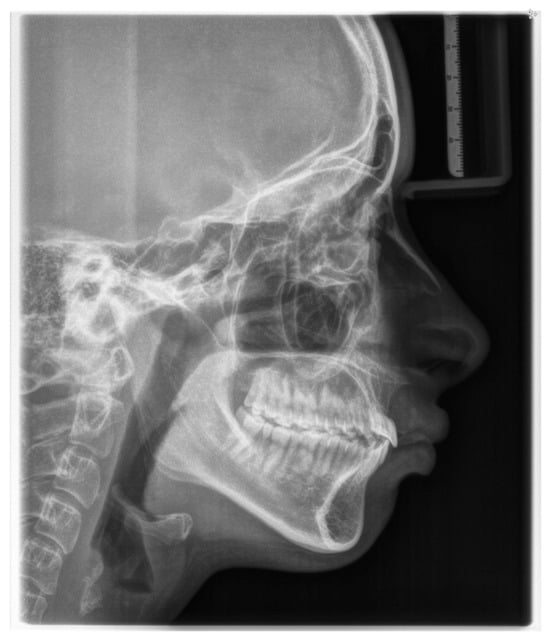

Figure 4. Pre-treatment lateral cephalometric radiograph.

According to latero-lateral teleradiography (Figure 4), she presented with an upper jaw retrusion combined with a lower jaw retrusion relative to the cranium (SNA = 81°, SNB = 73°, Wits appraisal of 7 mm) and a normal facial growth pattern (NS-Sar-ArGo-GoMe = 398.9°) with a normal mandibular plane angle (FMA = 25°, Gonial angle = 120°). Although the skeletal discrepancy was compensated by maxillary incisors’ retrusive inclination (upper incisor to SN = 89.48°, to NA = 1.55 mm) combined with normal mandibular incisors inclination (lower incisor to GoMe = 90°, to NB = 27°), an increased overjet of 15 mm was measured as reported in Table 1. Furthermore, a pretreatment lateral cephalometric radiograph revealed narrow airways.